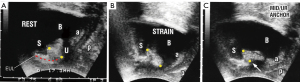

Preuves échographiques de la faiblesse du PUL comme cause d'IUE

La Figure 6 est une échographie transpérinéale d'une femme souffrant d'IUE. Au repos (Figure 6A) l'urètre est fermé. Sur la Figure 6B (tension), le PUL s'étend. Les parois vaginales antérieure et postérieure (a&p) sont étirées vers l'arrière et le bas pour ouvrir la paroi postérieure de l'urètre sur toute sa longueur. Dans la Figure 6C (ancrage mi-urétrale), une pince hémostatique (flèche blanche) insérée derrière la symphyse comme dans la Vidéo S2, soutient mécaniquement le PUL affaibli et rétablit temporairement la fermeture urétrale sur toute sa longueur et la géométrie urétro-vésicale normale lors de l'effort. Les parois vaginales antérieure et postérieure (a&p) sont tendues; l'urètre est fermé au niveau du col vésical et distalement.